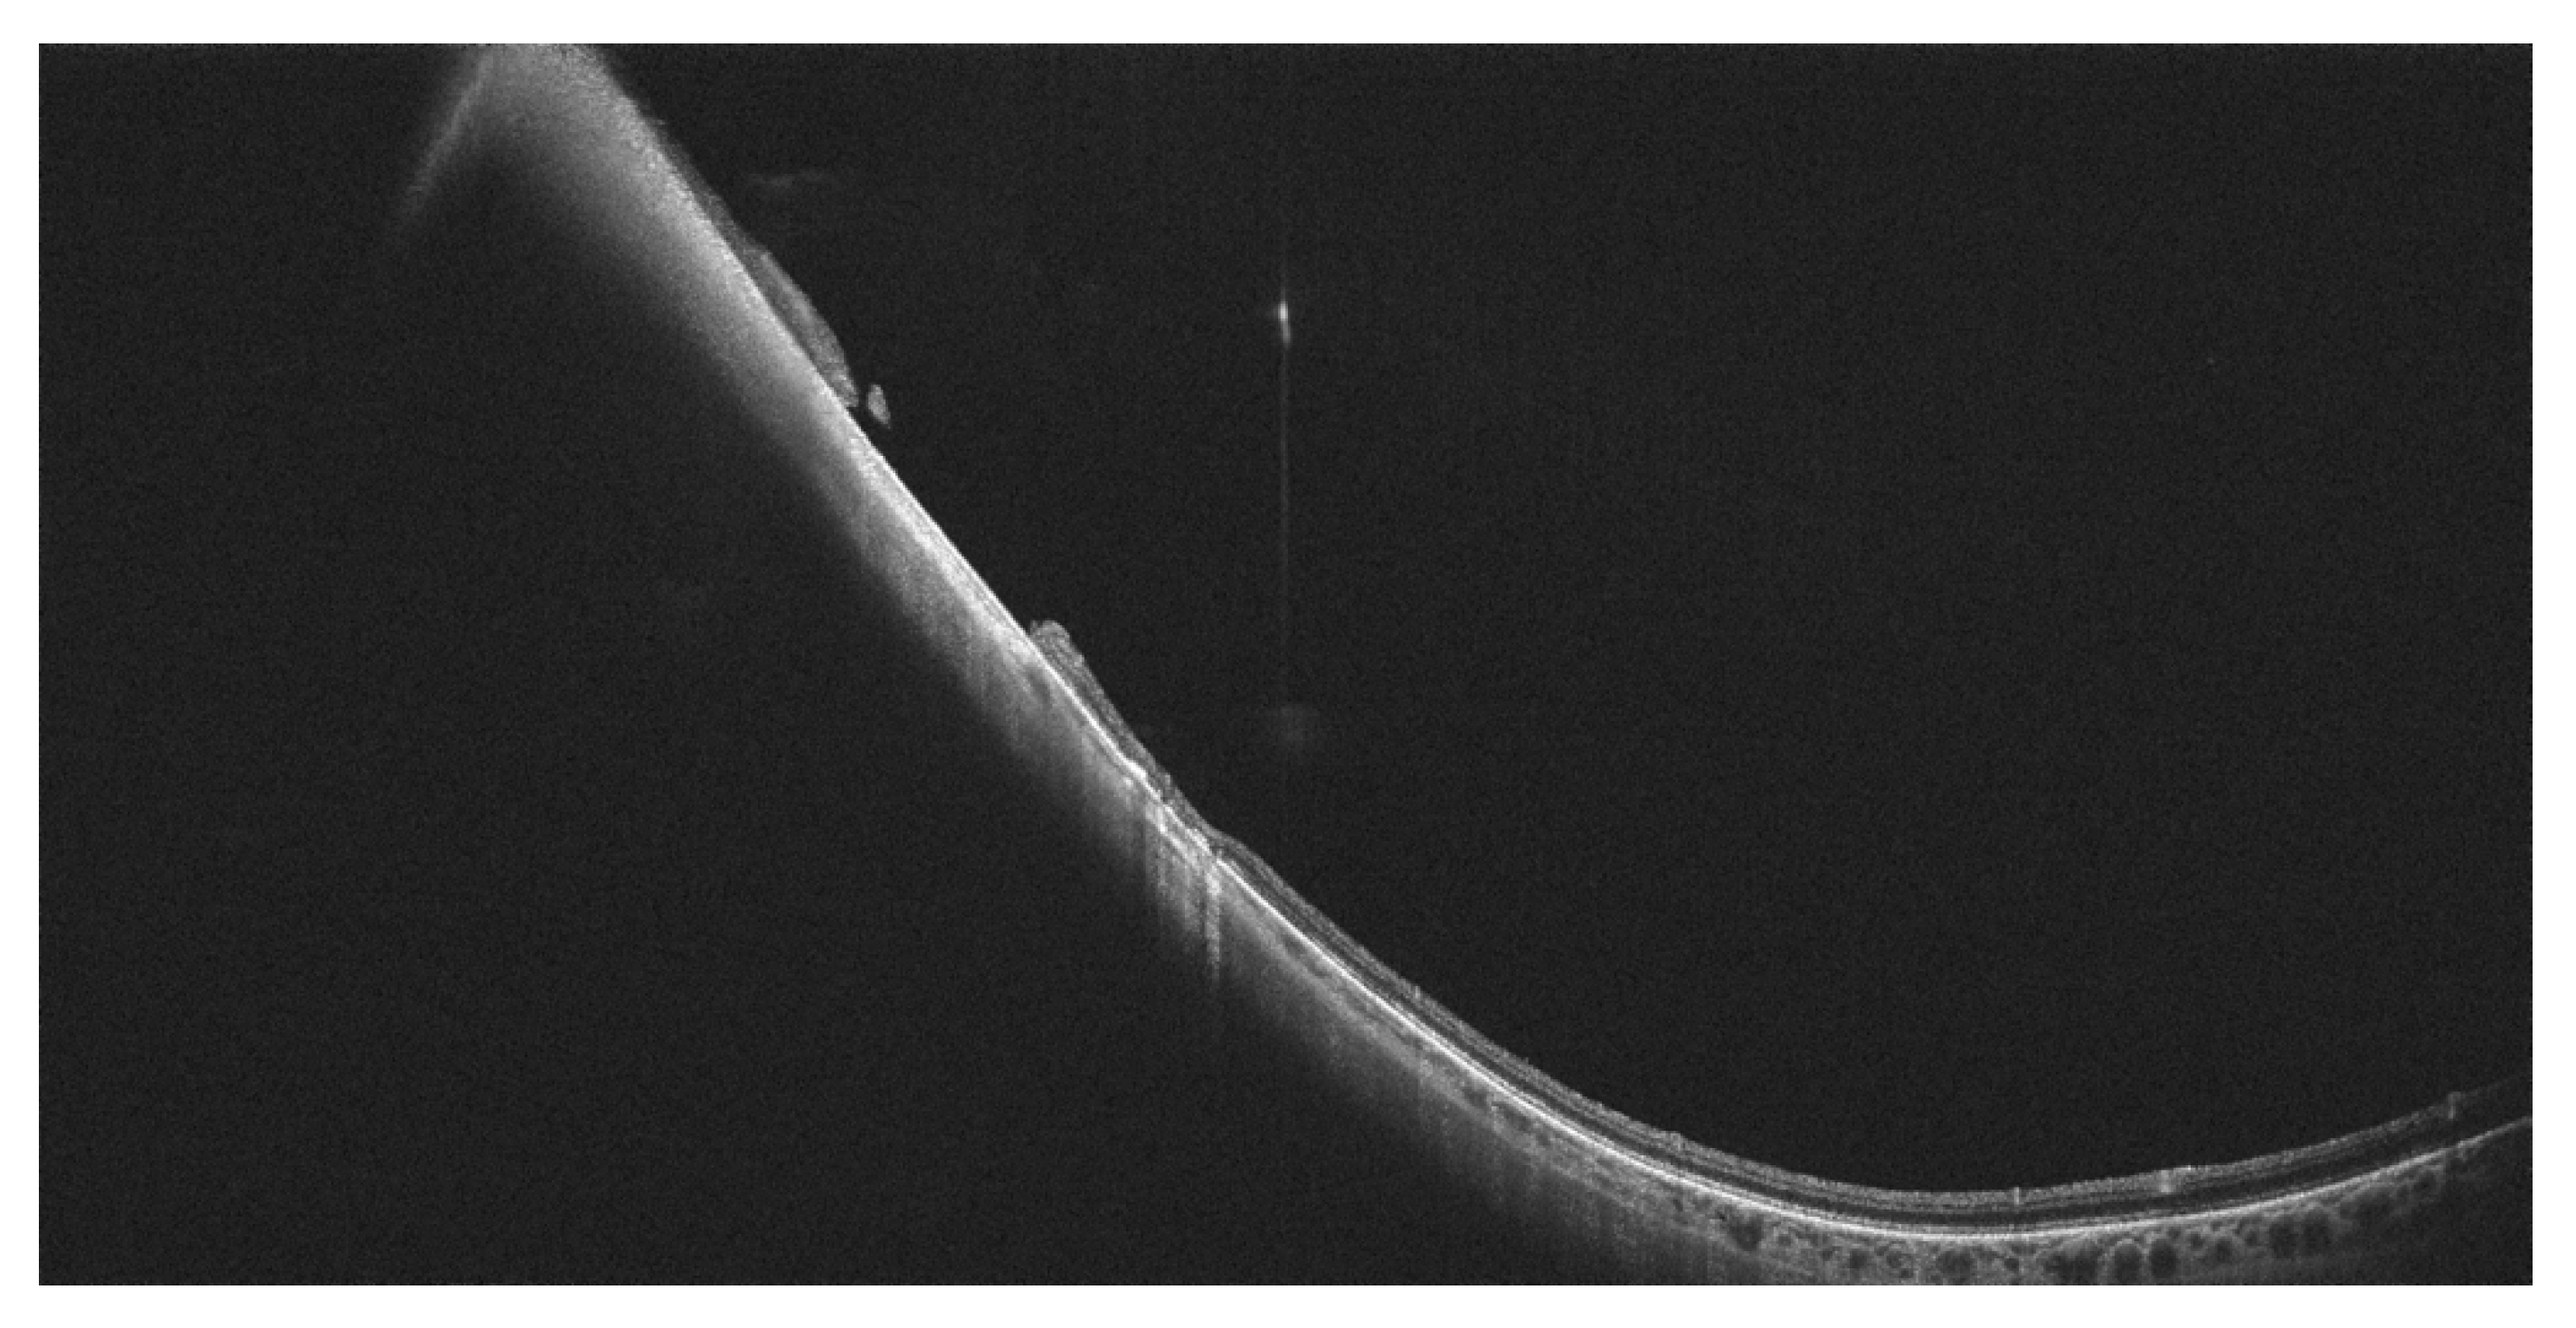

- Govetto, A.; Sebag, J.; Lucchini, S.; Ballabio, C.; Matteucci, M.; Ranno, S.; Carini, E.; Virgili, G.; Bacherini, D.; Radice, P. Imaging rhegmatogenous retinal lesions and peripheral vitreo-retinal interface with wide-field optical coherence tomography. Retina. 2023. [Google Scholar] [CrossRef]